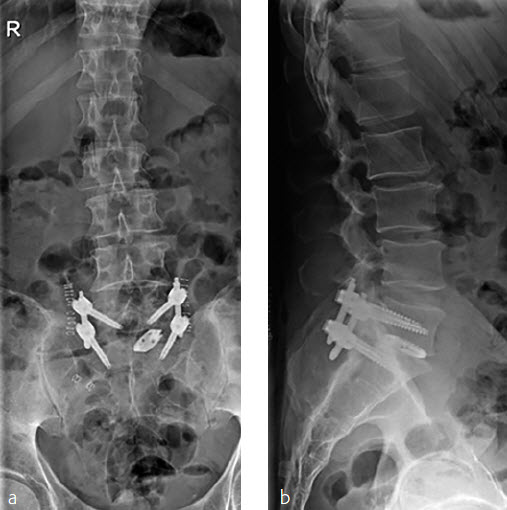

A 52-year-old male patient presented with low back pain and S1 radicular pain on the left side for 3 weeks. The laboratory tests of the blood showed enhanced inflammation signs. The MRI showed an infection of the L5/S1 disc (Fig 1). Indications for minimally invasive spondylodesis with intervertebral cage (Figs 2-6).